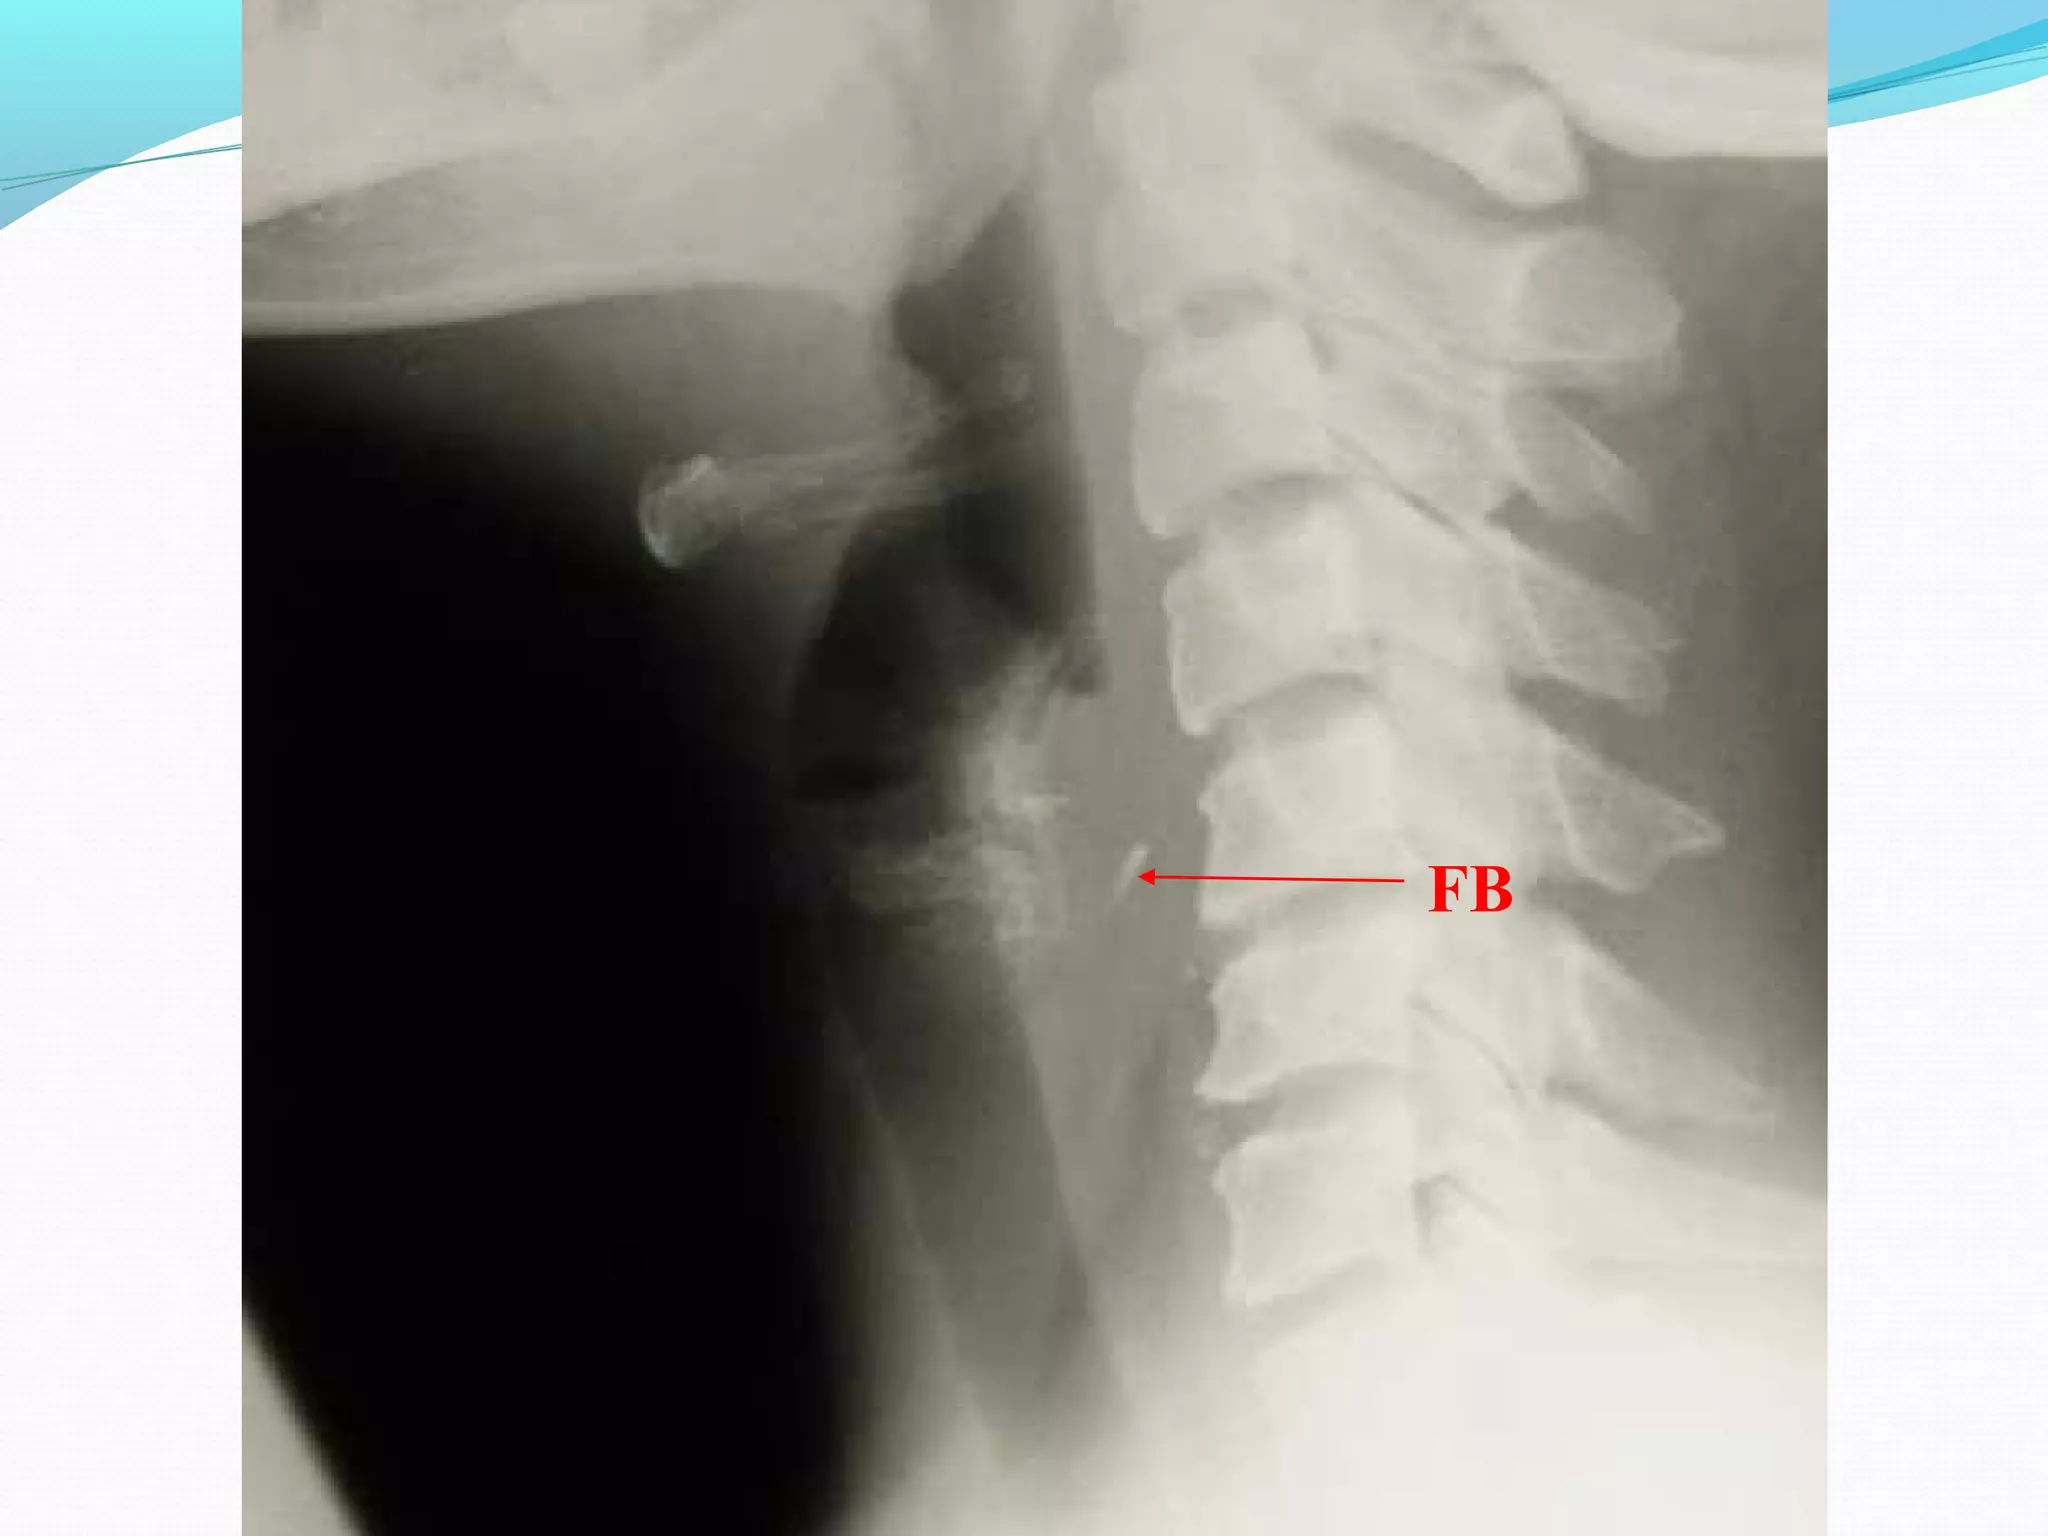

Epiglottitis

Indirect Laryngoscopy

Flexible Fiberoptic nasopharyngoscope

Lateral neck X-ray - thumb sign

Normal

epiglottis

Swollen